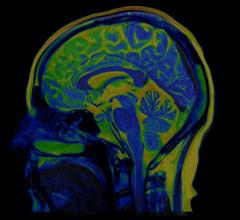

A 90-second brain acquisition with FDG radiotracer — comparison of digital (Vereos, left, 1 mm) and conventional (Gemini TF, 4 mm) images.

The digital technology underlying Vereos can provide the details that may escape analog systems, said Piotr Maniawski, director of clinical science for nuclear medicine at Philips Healthcare. Visualization using 4 mm cubes, which are typically delivered by analog systems, makes small lesions look spherical, he said. The very small voxels in digital images better visualize shapes and texture.

Maniawski explained that voxels in Vereos images are densified with data collected by the 23,000 solid-state sensors from individual scintillation events. This added data density allows Vereos to package data into voxel volumes of 2 mm — or even 1 mm — cubes. This data density gives shape and texture to structures in the images.